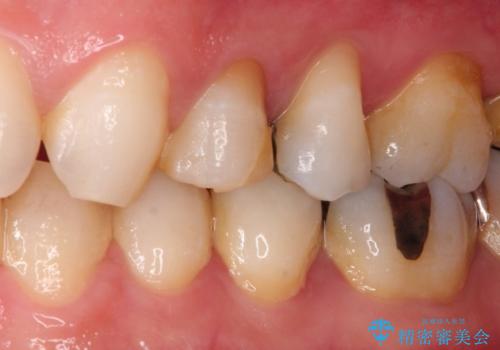

- 歯肉の下まで深く歯が折れたことを主訴に来院された患者様です。

かかりつけ医にて応急的に修復してますが根本的な治療を希望され、矯正的挺出を行ったのち、歯周外科を行い、歯冠修復をしております。

歯肉縁下の水平破折をきちんと治療するためには時間も費用もかかります。